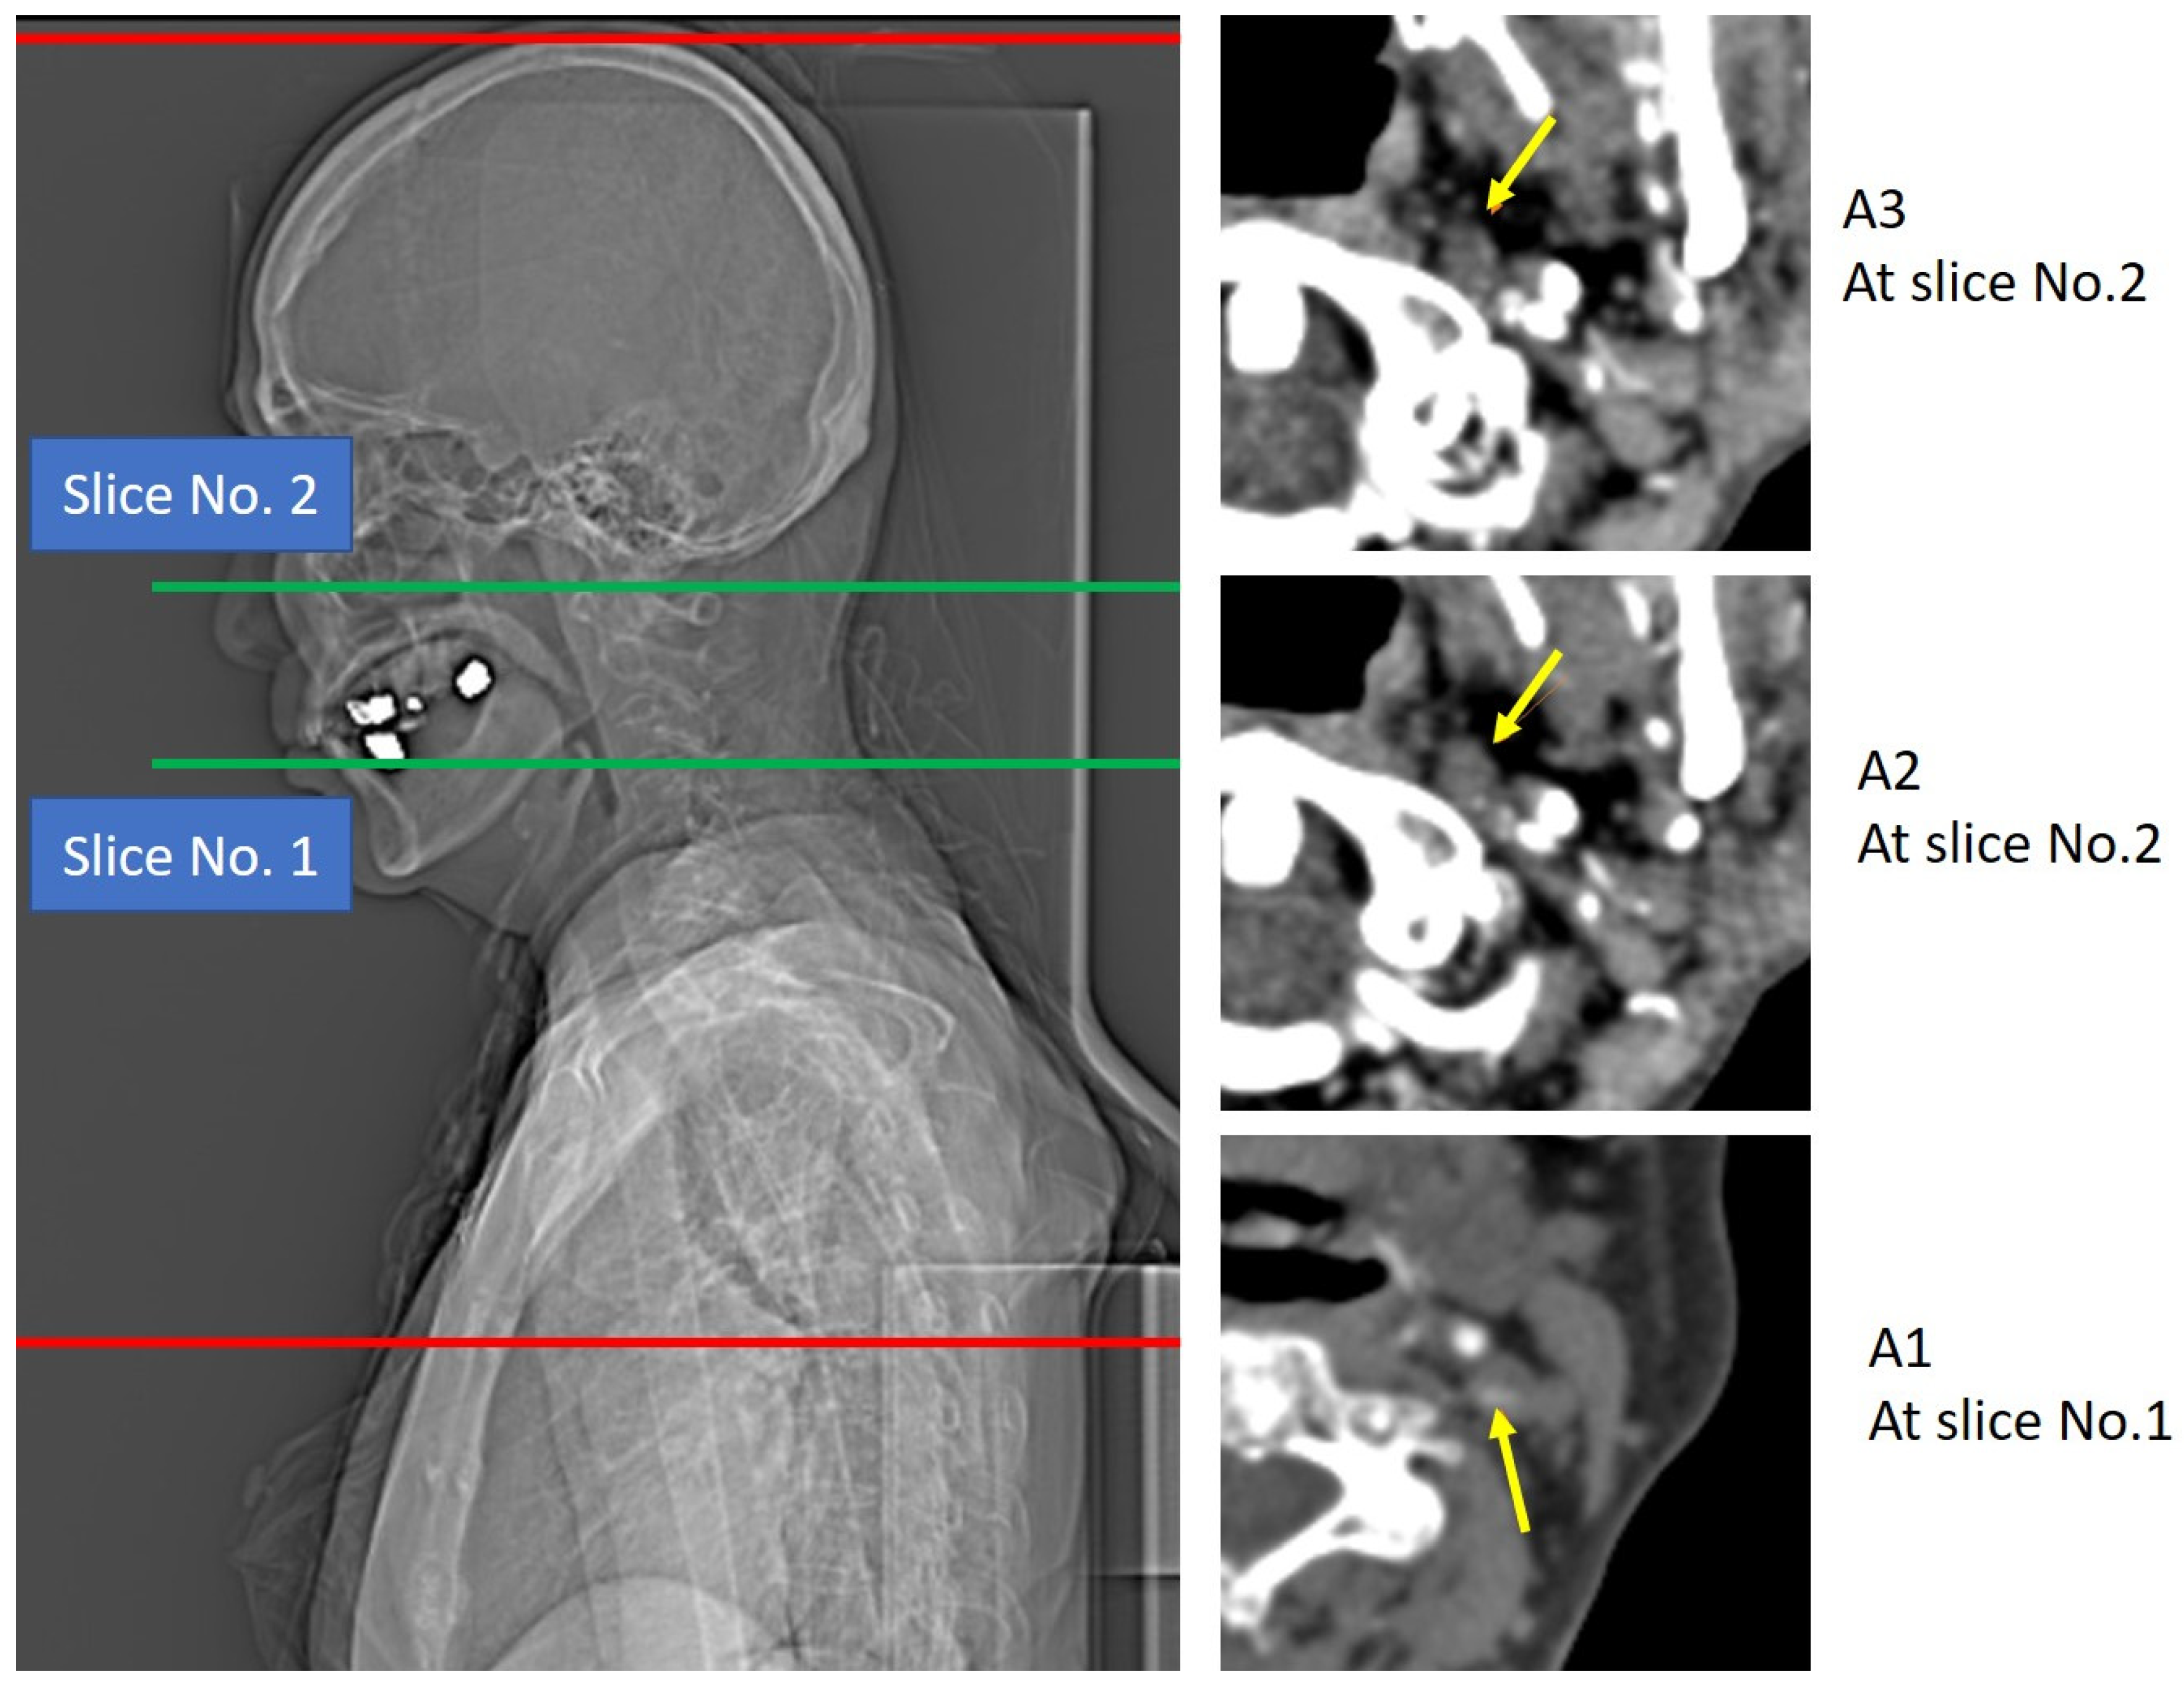

2.1. Procedure of Multiphase CTA

2.2. Multiphase CTA Measurement